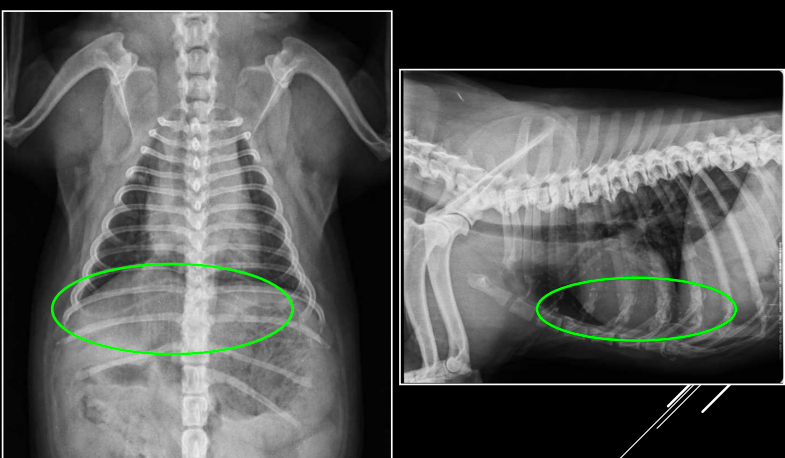

Orden de exploración de las estructuras extratorácicas

1. Pared torácica

- Tejido subcutáneo y piel deben visualizarse como opacidad homogénea de grosor uniforme.

- Gas (enfisema), mineralizaciones.

- Engrosamiento de piel: traumatismo, cuerpos extraños, hematoma, absceso o neoplasia.

2. Costillas

- Trece pares, simétricas, densidad homogénea.

- En animales geriátricos, uniones costocondrales con mineralizaciones irregulares (“formaciones en roseta”).

- Alteraciones: fracturas o neoplasias.

3. Esternón

- Escasas alteraciones significativas.

- Posibles: neoplasias, infección, pectus excavatum (Problemas aspiratorios, puede ser congenita) o pectus perinatum (poco frecuentes, perinatum aun menos)